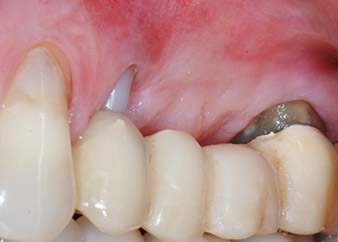

Un mois plus tard, le jour de l'intervention, la douleur et l'inflammation sur la dent 24 étaient minimes mais une mobilité de classe 2 de Miller était toujours observable. Après ouverture des lambeaux et nettoyage des tissus périapicaux et périradiculaires infectés, l'étendue du défaut osseux est devenue parfaitement visible (Figures 2 et 3).

À la racine de la dent, il manquait la totalité de l'os vestibulaire et distal. L'attache était essentiellement limitée à la racine palatine, venant ainsi confirmer le pronostic défavorable initial. La dent 27 présentait également une attache horizontale réduite et une raréfaction apicale minime (cf. Fig. 1), sans symptômes cliniques.

Nous avons toutefois maintenu notre projet initial de conservation des deux dents comme piliers temporaires d'un bridge pendant la période de six mois nécessaire à l'ostéointégration des implants. À la prochaine incision, la situation devrait être réétudiée. Premièrement, afin de gérer le problème endoparodontal, la surface de racine restante a été soigneusement débridée à l'aide d'un équipement piézoélectrique (Piezomed, W&H, utilisé avec l'insert en forme de spatule S1, initialement conçu pour limer la paroi sinusienne latérale) (Fig. 4).